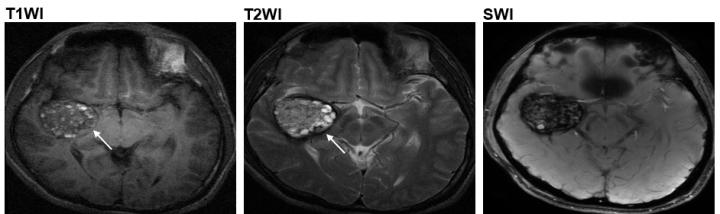

image: The popcorn-like lesions (as indicated by the arrows) in the brain arteries of Type II CCM patients.

Now, using next-generation sequencing and computational approach, a research team led by Prof. WANG Jiguang, Assistant Professor from HKUST's Division of Life Science and Department of Chemical and Biological Engineering, in collaboration with Prof. CAO Yong from the Beijing Tiantan Hospital, analyzed the genomic data of 113 CCM patients and identified another mutation called MAP3K3 c.1323C>G, which is found to be responsible for almost all the tested cases who developed popcorn-like lesions in their brain arteries - the most common one among the four types of CCM lesions (type II CCM).

At present, magnetic resonance imaging (MRI) is a commonly used non-intrusive means that doctors can base upon for diagnosis and treatment. However, the MRI images can only tell the size and type of the lesions, but not the gene responsible for the problem - which can only be ascertained by surgery and laboratory tests. Now, the HKUST research team designed a computational method that could help assess the probability of connection between the lesion shown in the MRI image to the genetic mutation MAP3K3 c.1323C>G. So CCM patients with this gene mutation may be able to receive more targeted treatment without having to undergo surgery - which could bear serious risks including cerebral hemorrhage or new focal neurological deficits.